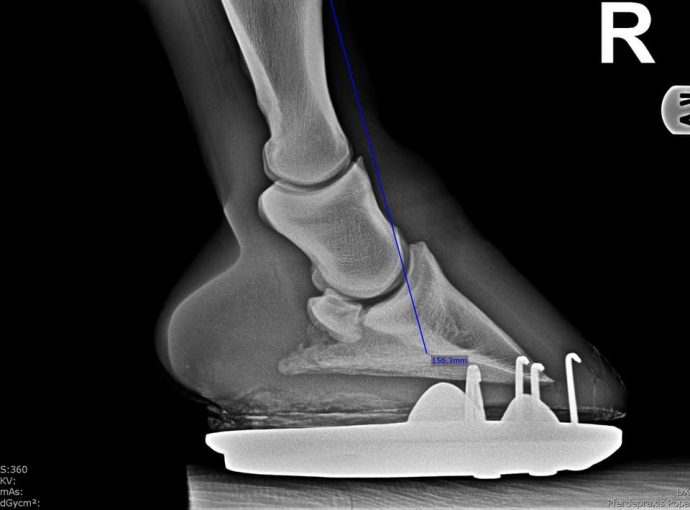

Zwischen den Bilder sind 6 Wochen. Auch wenn Klebebeschläge einfach in der Anwendung scheinen, sind auch diese eine Katastrophe fürs Pferd, wenn das Ausschneiden überhaupt nicht funktioniert. Ich kann nur immer wieder dazu raten immer den Fachmann/Frau fragen. Dieses Pferd sollte zum Schlachter.